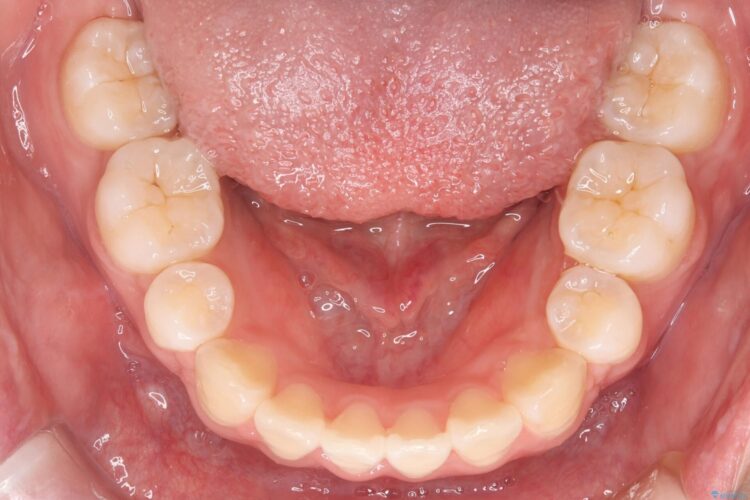

上下4番目の歯を抜歯してガタつきを改善しながら口元を下げる治療計画を立てました。

抜歯矯正で口元を下げたことで、Eラインが大変綺麗になりました。